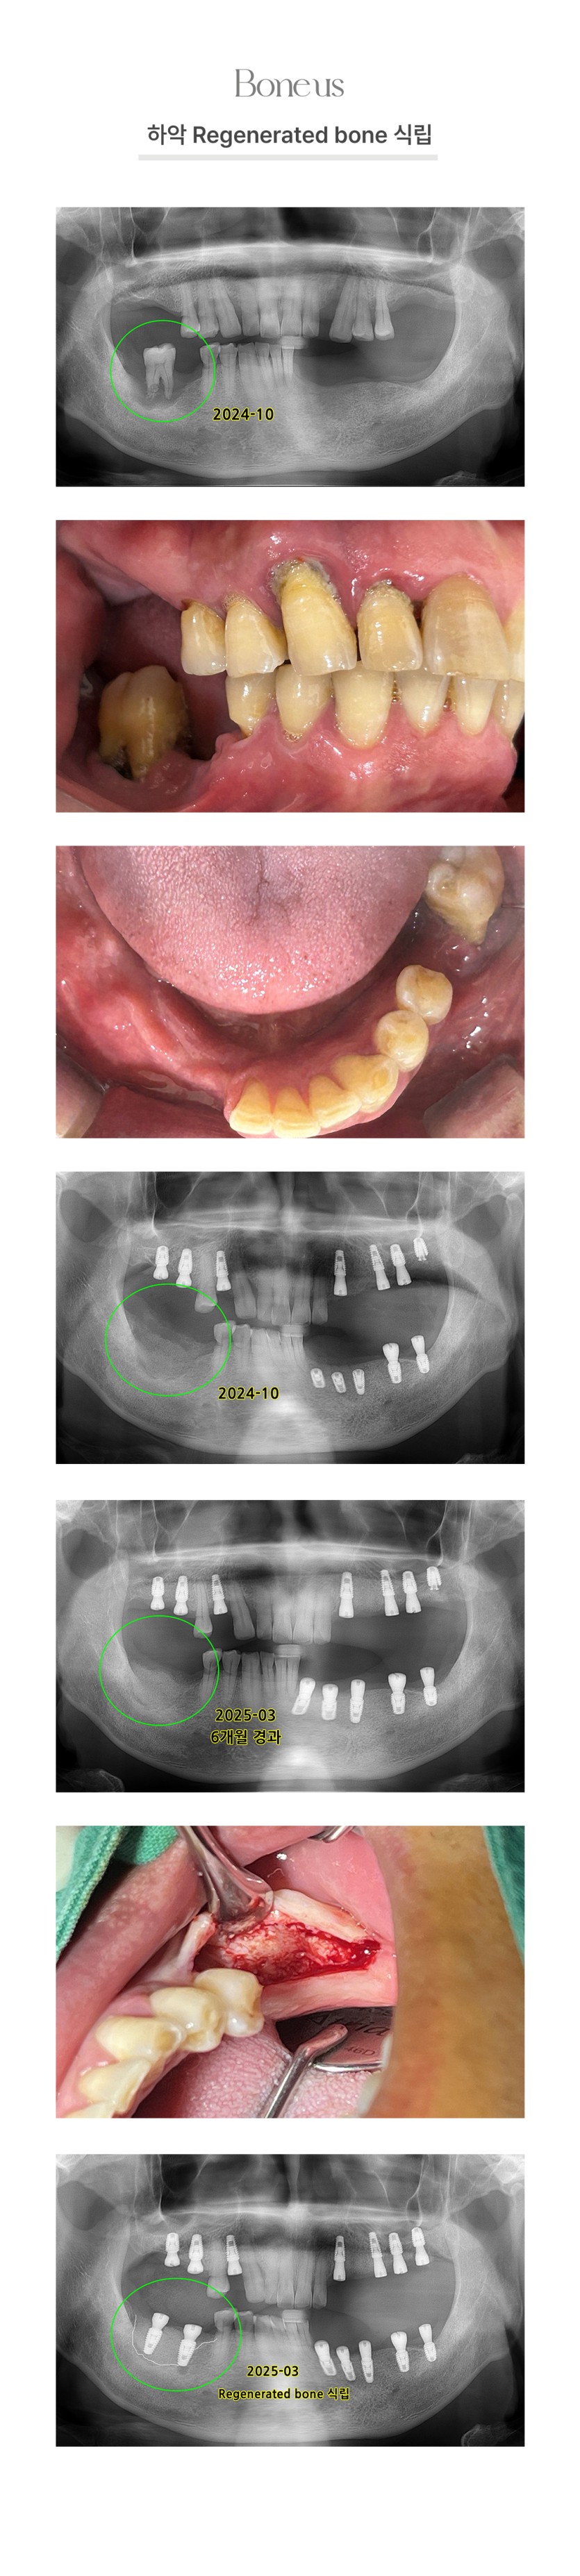

하악 Regenerated bone 식립 1